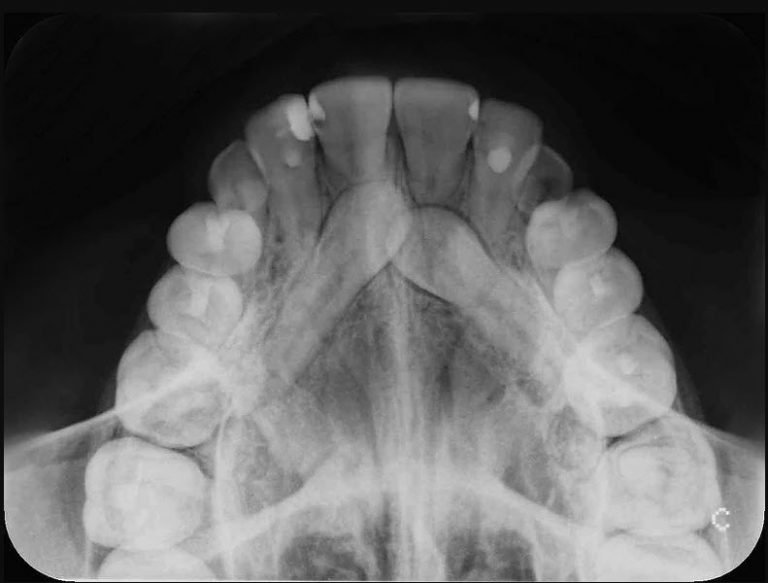

Las radiografías dentales son un tipo de imagen de los dientes y la boca. Los rayos X son una forma de radiación electromagnética de alta energía y penetran el cuerpo para formar una imagen en una película o en una pantalla. Las radiografías pueden tomarse de manera digital o en una película.